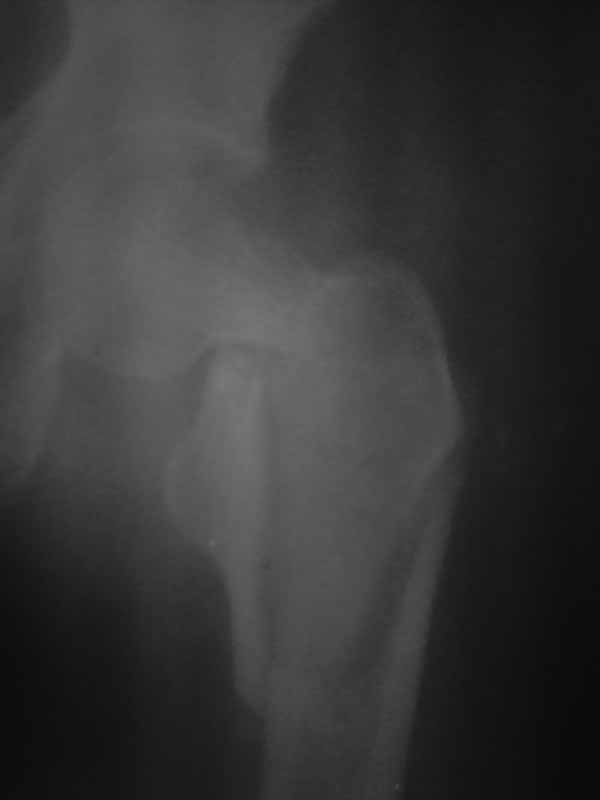

Доброго времени суток уважаемые коллеги!! Если бы перелом был чрезвертельным то все примерно было бы понятно. Гамму пациентка не купит, больница тоже ее не купит. Я попытался прислать еще снимки гляньте пожалуйста. Можетбыть вести действительно консервативно чтобы прирос фрагмент межвертельного перелома а потом поднять речь об эндопротезировании, ища квоты?! DXS - я говорю об динамическом бедренном винте с накладкой. Единственно что есть это LSP пластины да в шейку загнать винты АО. А больница наша скоропомощная в г.-герое Москва №68. Спасибо всем ответившим и прочитавшим. Случай не простой.

Ну снимки-то нормальные можно сделать в скоропомощной больнице, т.е. очевидно располагающей не просто рентгееновской службой, а даже круглосуточной? Если не с первой, так с пятой попытки?

И в городах даже менее героических, чем Москва, известно, что для около- и внутрисуставных переломов очень информативна компьютерная томография.

Обсуждать возможные варианты операции на основе несколько раз сфотографированной одной и той же мутной картинки вряд ли продуктивно.

Нет КТ - качественный Рн нужен. Консервативное лечение здесь не рассматривается, как однозначно калечащее. Видно - нужно быть готовым к открытой репозиции. Винты не обеспечивают достаточной стабильности при такой линии излома. И, даже если бы была возможность ИМ фиксации, я бы предпочёл Динамический Бедренный Винт (так правильно?) в этом случае. Черкните мне, или позвоните, если нужна поддержка, приеду, помогу по соседски-то. Вы же в Коньково? Андрей

Этот случай не является типичным, я бы рассматривал его с точки зрения механики как комбинацию (редкую, надо сказать, комбинацию) латерального и медиального переломов. Если я правильно могу прочитать представленные рентгенограммы, конечно. И нестабильным как раз в данном случае является медиальный компонент повреждения. Поэтому выбор технологии диктуется медиальым, сложным компонентом. Для латерального по большому счёту всё равно - гвоздь или Динамический Бедренный Винт. Для базисцервикальной шейки же гвоздь не даёт особых преимуществ. Репозиция, скорее всего, будет октрытой. Поэтому, DHS в комбинации (если войдёт)с дополнительным антиротационным винтом. Но, -прежде всего, рентгенография нужна приемлемого качества. Так я бы рассуждал, если бы это был наш пациент. С уважением, Андрей